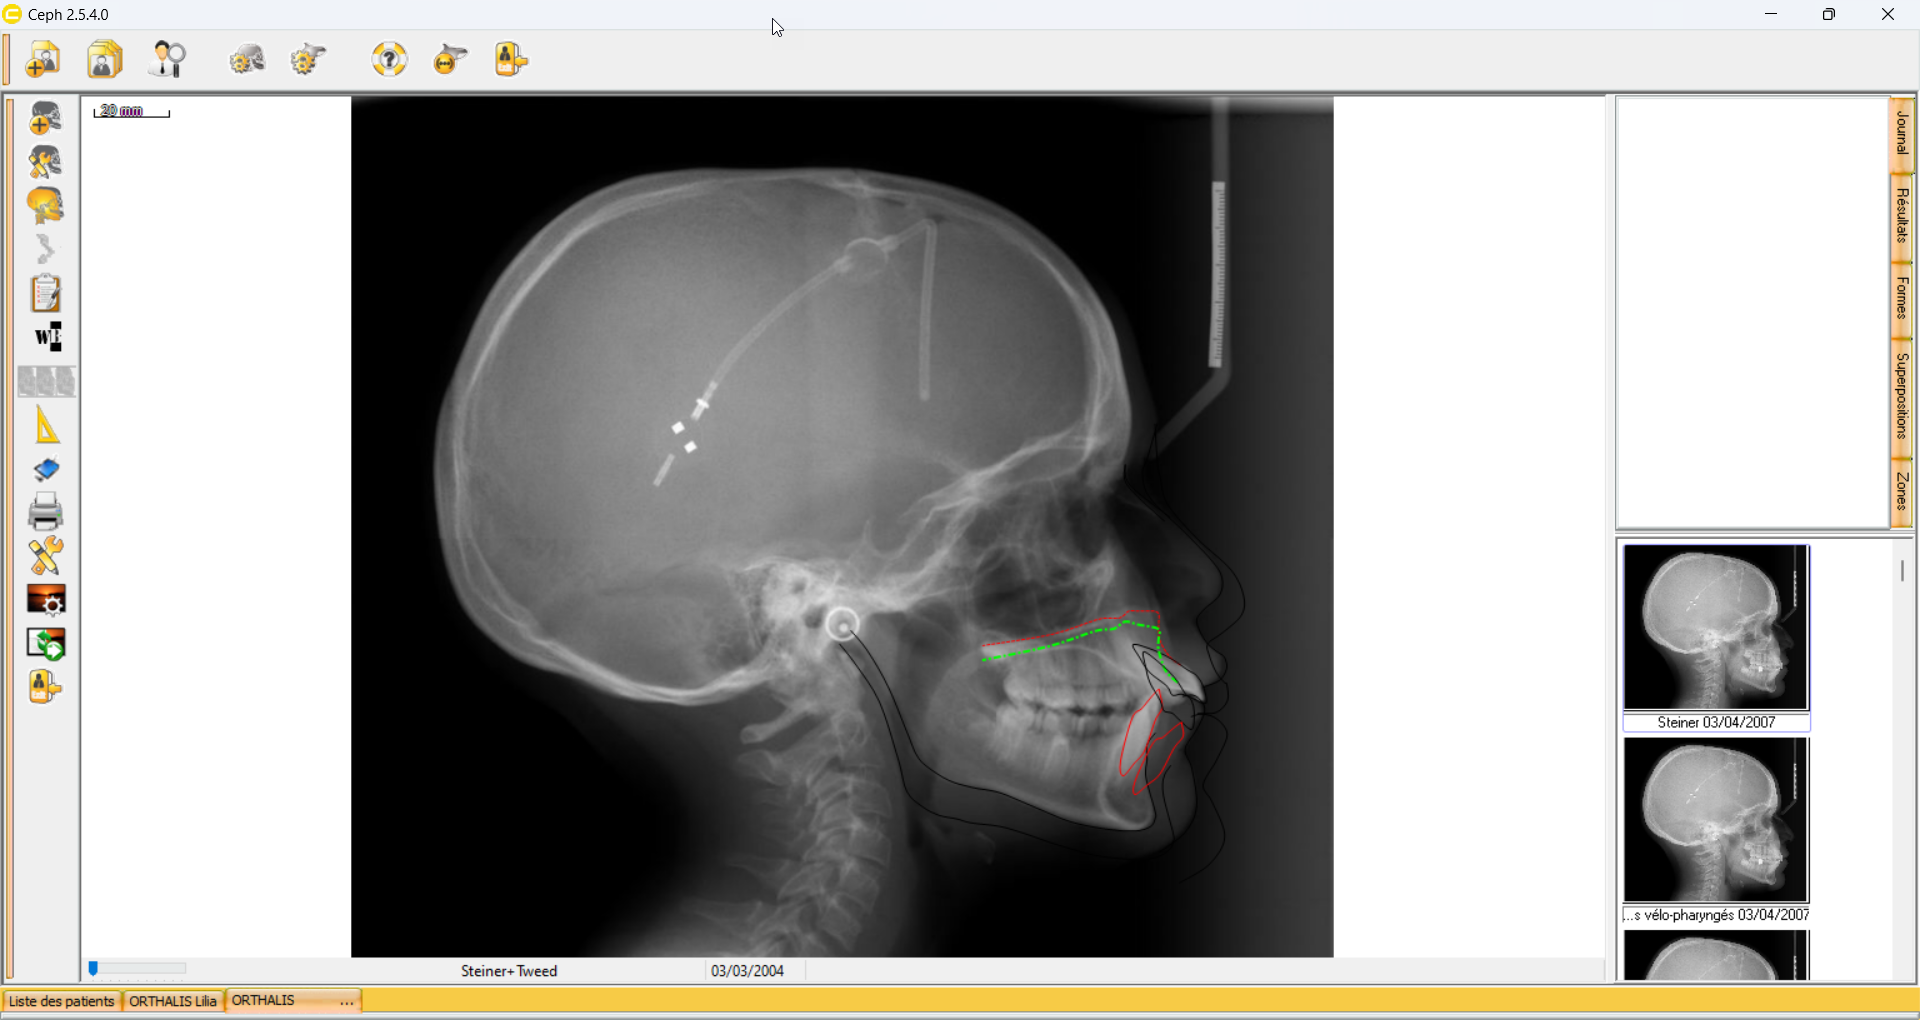

Ouvrez une analyse de votre patient (ici dans cette exemple le modèle d'analyse est Steiner + Tweed, de 2004).

Nous allons maintenant cliquer sur le bouton Superposition d'analyse situé dans la barre d'outil de gauche.

Le logiciel Ceph va vous identifier, automatiquement, les analyses présente sur ce patient, de même modèle.

Ici sur cet exemple, il identifie une analyse Steiner + tweed de 2007, pour ce même patient.

Nous sélectionnons analyse proposé puis nous faisons Suivant.